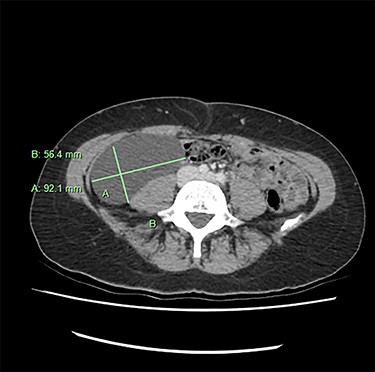

We present an extremely rare and isolated case of primary mixed serous and mucinous cystadenoma in a 49-year-old otherwise fit and healthy female patient. She was referred to our consultant with a history of discomfort on the right side of her abdomen for few years, which increased gradually with no other complains. The patient had further investigations conducted including computed tomography (CT) (Figs 1 and 2) that demonstrated the position and size of the lesion. The magnetic resonance imaging (MRI) revealed a large cystic lesion in the right retroperitoneal region shown in Figs 3 and 4. Her full blood count, inflammatory markers, urea and electrolytes and liver function tests were within the normal limit. Consequently, the patient had a laparoscopic resection of an isolated retroperitoneal cyst. At surgery, the cystic lesion seemed to be arising from mesentery and the lesion was dissected intact and completely excised. Histopathology revealed a benign mixed serous and mucinous cystadenoma as shown in Fig. 5. The patient was discharged from the hospital with no complications and fully recovered on follow-up review. Patient was discussed in a multidisciplinary team meeting and the recommendation was for no further management.